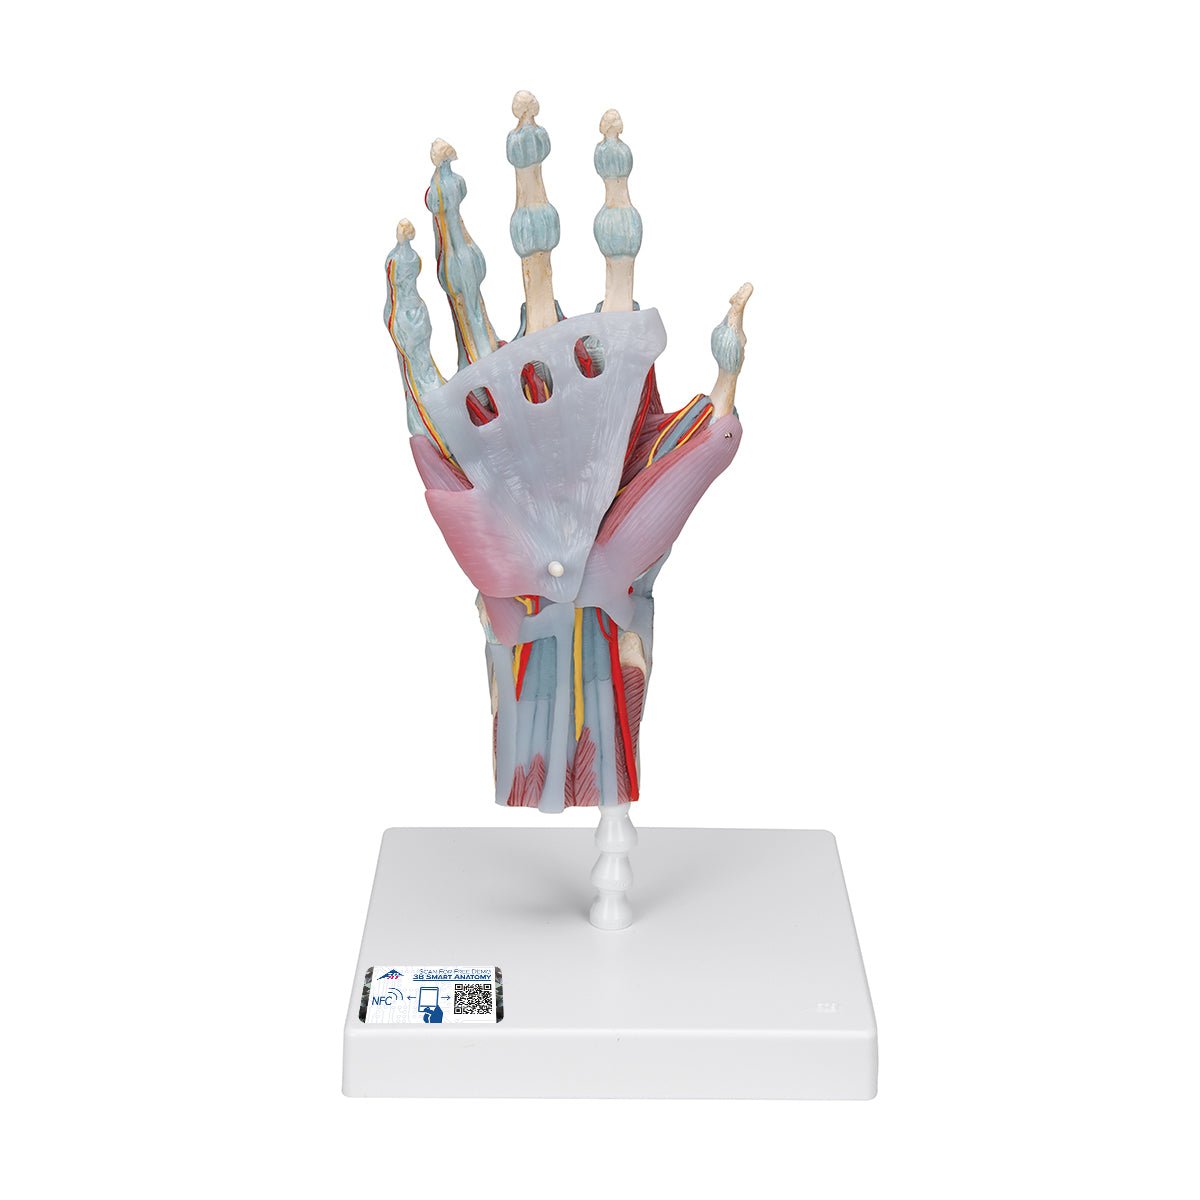

Salg af anatomiske modeller er det bærende element i eAnatomi, selvom vi også bruger mange ressourcer på at udvikle vores egne anatomiske materialer som fx plakater. Anatomiske modeller anvendes til forskellige formål og kan både vise afgrænset væv, organer samt organsystemer. Søger du en simpel model af knoglevæv eller måske en avanceret torso-model baseret på MRI teknologi, kan du finde det hele på eanatomi.com.